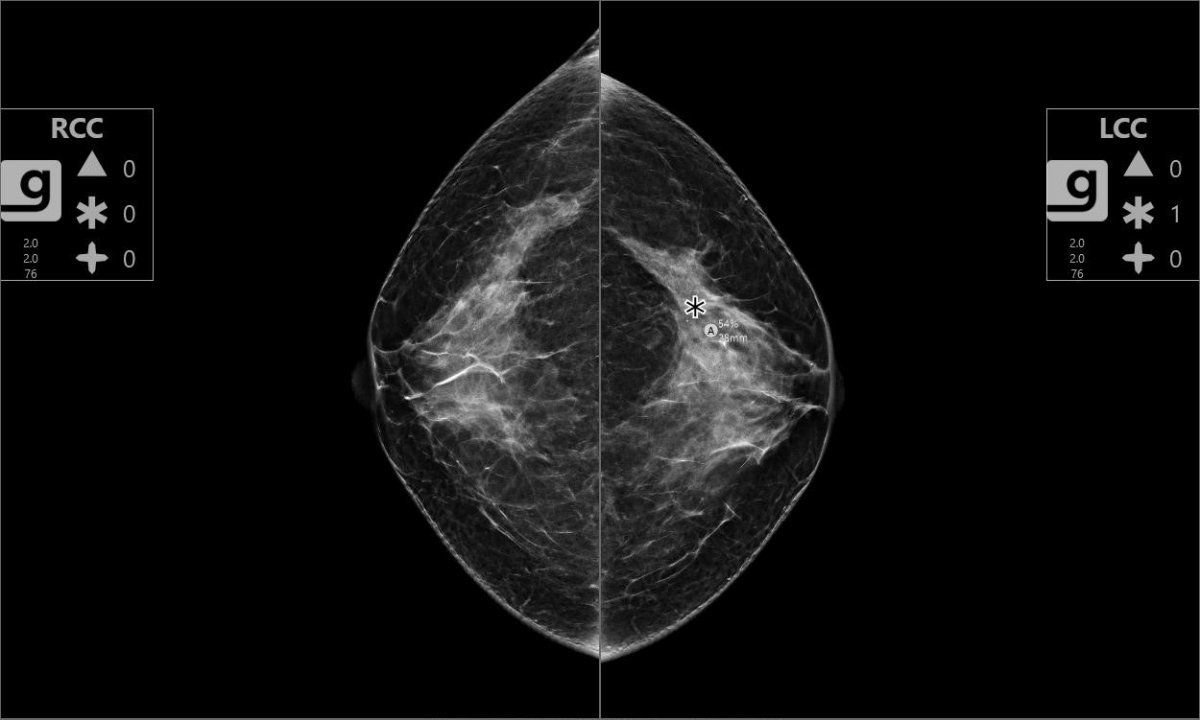

3D 유방영상 판독 보조 솔루션 Genius AI 2.0. 왼쪽 유방에서 발견된 병변의 위험도를 평가한 사진. 제공=동아대병원

여성 건강 진단 전문기업 홀로직 코리아는 경남 지역 최초로 부산 동아대학교병원에 인공지능 기반 유방암 진단 보조 솔루션인 Genius AI 2.0을 공급했다고 밝혔다.

해당 솔루션은 미국 FDA 승인을 받은 첨단 AI 기술로, 3D 유방촬영 영상을 분석하여 악성 종양의 검진 정확도를 높이고 판독 효율을 향상시키는 데 도움을 준다. 지난 4월 3D 유방촬영술의 급여화 전환 이후3D 유방촬영술(디지털 유방단층촬영술)의 활용이 확산되고 있는 가운데, Genius AI 2.0은 영상의학과 전문의의 진단을 보조해 판독 피로도를 줄이고, 놓치기 쉬운 병변을 놓치지 않도록 돕는 역할을 할 것으로 기대된다는 것이 병원 측의 입장이다.

박일철 동아대학교병원 영상의학과 교수는 “유방촬영술에서 2D 검사와 3D 검사의 차이는 흉부 X-ray와 흉부 CT의 차이와 유사하다. 일반적인 2D 검사에서는 병변이 정상조직과 겹쳐서 잘 안 보이는 경우가 많고, 인공지능도 발견을 못 하는 경우가 있다. 하지만 3D 검사에서는 입체적인 영상을 통해 더욱 정확한 진단이 가능하다” 며, “Genius AI 2.0은 3D 유방영상의 병변 탐지 민감도를 높여줄 뿐 아니라, 판독에 드는 시간을 줄이는 데도 유의미한 효과를 보이고 있다”고 말했다.